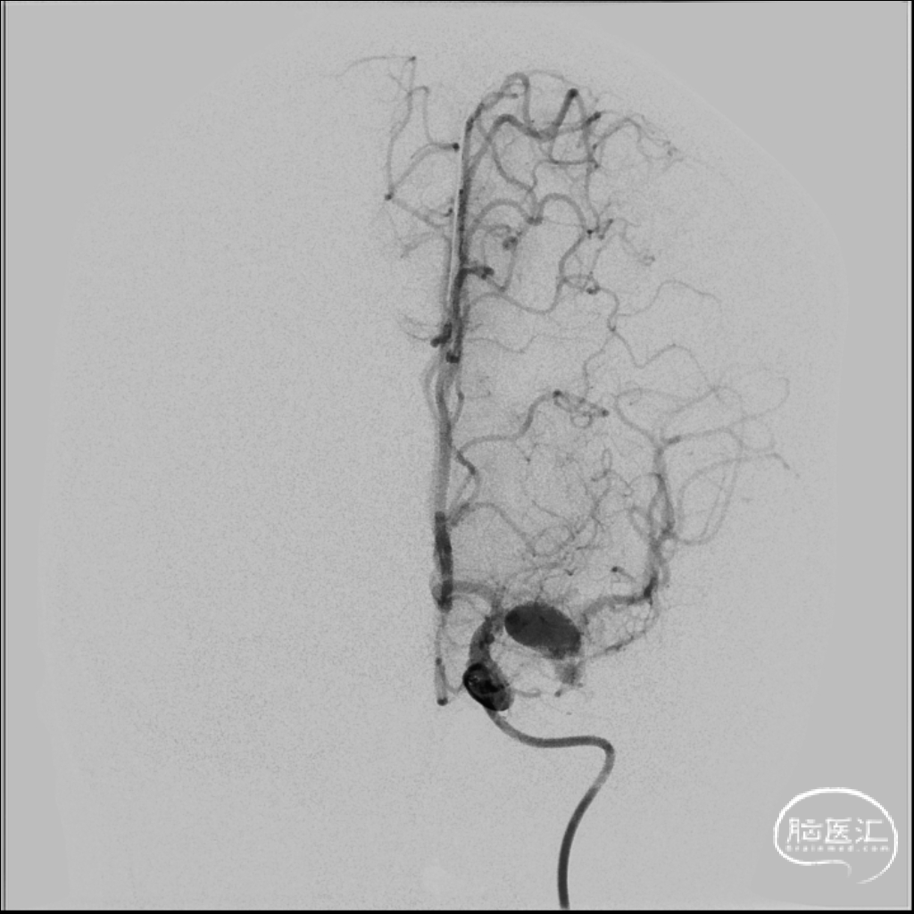

2024年4月1日 DSA

L ICA

L ICA 3D

AN长径9.14mm

远端血管大脑中直径2.34mm、近端颈内末端4.25mm